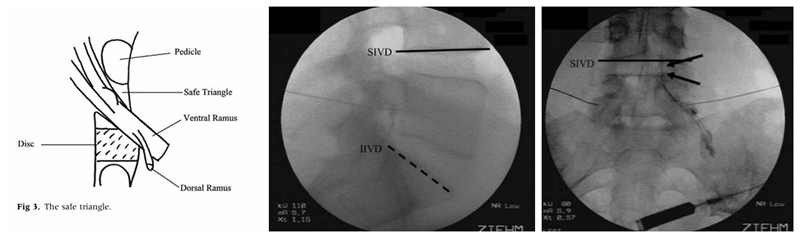

既然我们只需要把药物注射至神经根的周围而没必要注射至神经根鞘膜内,那么有没有一个更安全固定的穿刺点可以选择呢?答案是肯定的。Bogduk等提出了一种新的注射方法,该方法是将穿刺靶点设定在神经根的肩上,椎弓根的下方,Bogduk将这种方法称之为Sub-pedicular(SP)入路。穿刺的靶点称为安全三角(safe triangle):即椎弓根的下缘水平线,椎间隙外侧的垂直线和出椎间孔神经根的外缘线。该穿刺靶点有明确的骨性结构作为标志,可在影像引导下进行,同时将穿刺针尖远离了神经根。因此,提出了MRI椎间盘退变分型的Pfirrmann教授也发文力挺该方法,他认为在影像引导下采用这种方法进行脊柱注射术,是安全和精确的(safe and accurate)。SP入路很快便得到了广泛的认可和推广,至今仍有部分疼痛科医师使用。

图5